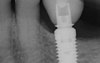

- Cas 1 :

Ce patient de 58 ans est venu consulter en raison d’un écoulement de pus au niveau de son implant remplaçant sa deuxième molaire inférieure. Le patient ne se passe pas de brossettes entre ses implants.